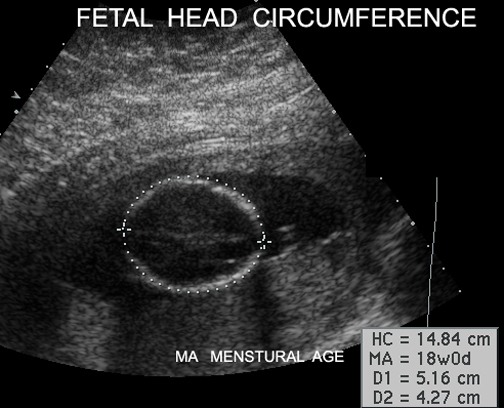

Fetal head circumference Answer

List the items measured by ultrasound Answer

Measurements Answer